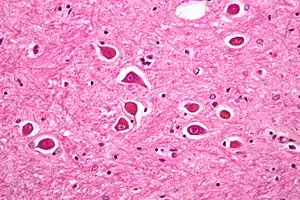

| Micrograph of Alzheimer type II astrocytes, as may be seen in hepatic encephalopathy | |